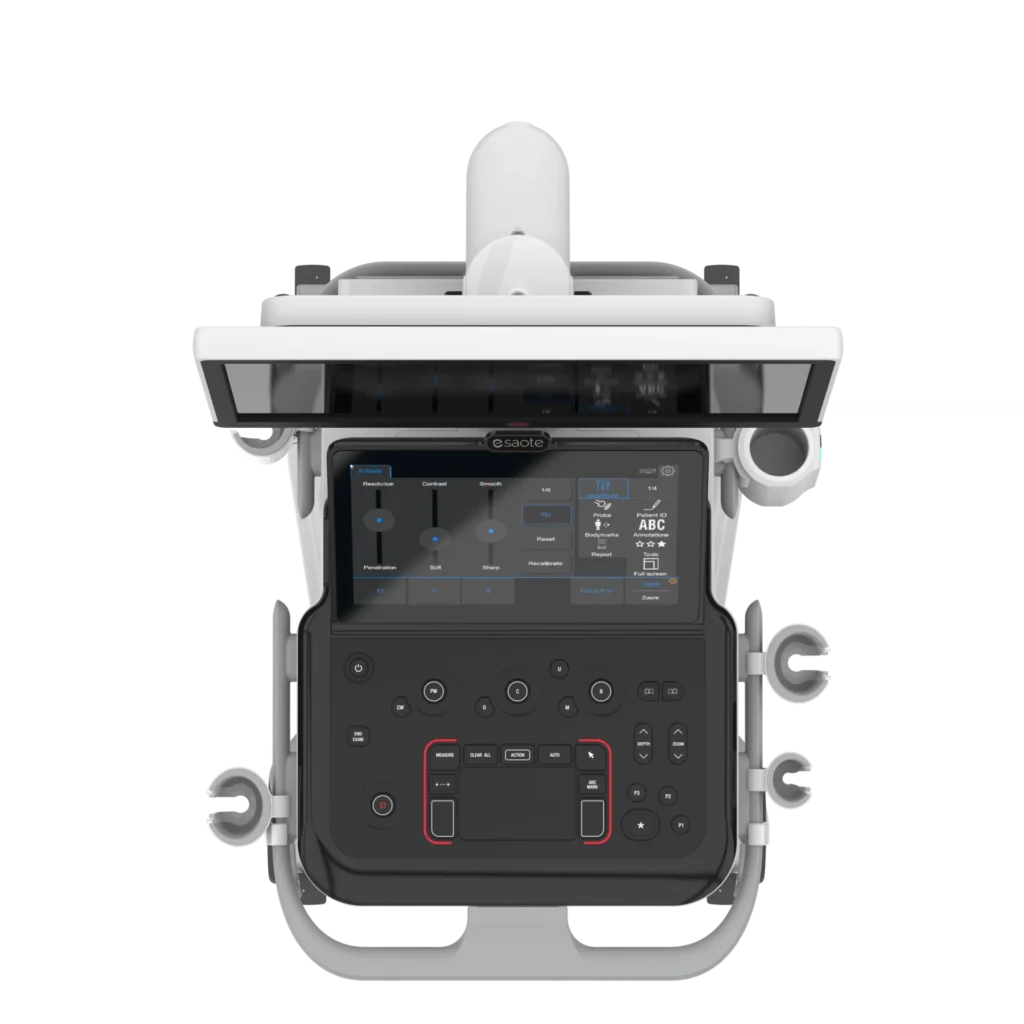

MyLab™ A50 je moderní ultrazvukový systém navržený pro každodenní klinickou praxi. Kombinuje vysokou kvalitu zobrazení, intuitivní ovládání a flexibilitu použití napříč různými medicínskými obory. Díky důrazu na efektivitu workflow a mobilitu pomáhá zjednodušit práci zdravotnického personálu a zároveň zvyšuje komfort vyšetření pacientů.

•13,3″ širokoúhlý dotykový displej

Multifunkční displej ve stylu tabletu pro snadné a intuitivní ovládání.

•21,5″ LCD monitor

Velký, výškově nastavitelný monitor s detailním zobrazením pro přesnou diagnostiku.

Moderní a promyšlený design

MyLab™ A50 je navržen jako spolehlivý partner pro každodenní klinickou praxi. Díky důrazu na ergonomii, jednoduché ovládání a efektivní workflow zvyšuje produktivitu práce a usnadňuje manipulaci s daty, jejich správu i sdílení.

MyLab™ A50 je dostupný ve dvou variantách ovládacího panelu, které se přizpůsobí různým pracovním stylům a preferencím uživatelů. Každá konfigurace nabízí specifické výhody – od jednoduchého a přehledného řešení až po pokročilé ovládání s důrazem na maximální komfort a efektivitu práce.